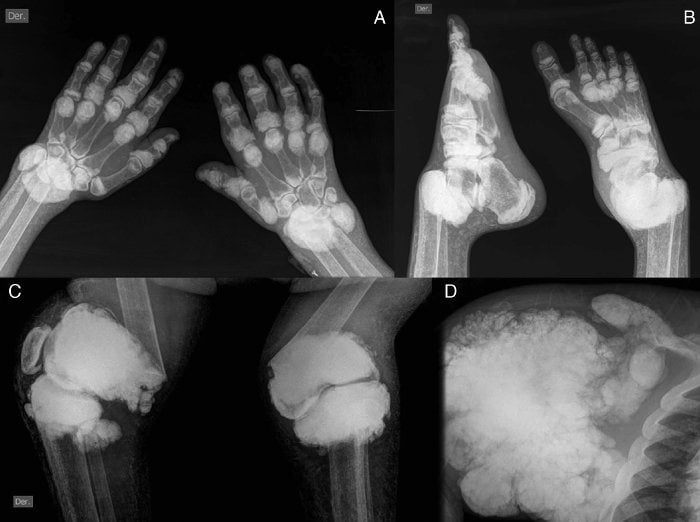

Обнаружить кальциноз суставных хрящей и периартикулярных тканей можно с помощью визуализирующих методов исследования. Наиболее простой — рентгенография. Выраженность клинической картины заболевания обычно не зависит от количества и размера кальцификатов. Часто множественные отложения солей не вызывают никаких симптомов, а типичные признаки артропатии возникают при отсутствии отложений.

Рентгенография позволяет выявить только крупные кальцификаты. А вот небольшие отложения солей можно обнаружить только с помощью УЗИ. Этот метод более чувствительный и специфичный при диагностике артропатий.

| Изменения на рентгенограммах | Появление асимметричных узловатых образований в тканях. На поздних стадиях наступает деструкция хрящей и костей, а кристаллы мочевой кислоты откладываются в костях | Кальцификация хрящей, суставной капсулы, сухожилий и периартикулярных тканей | Отложение солей в околосуставных тканях и местах крепления сухожилий к костям. При рентгенографии позвоночника в его мягких тканях также выявляют кальцификаты |